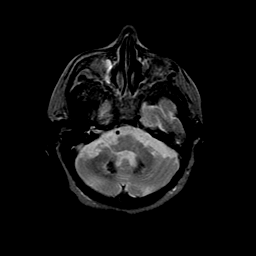

Basal Ganglia Calcification: T2-weighted MR -- Slice #4

[Home][Help][Clinical] Slice 4